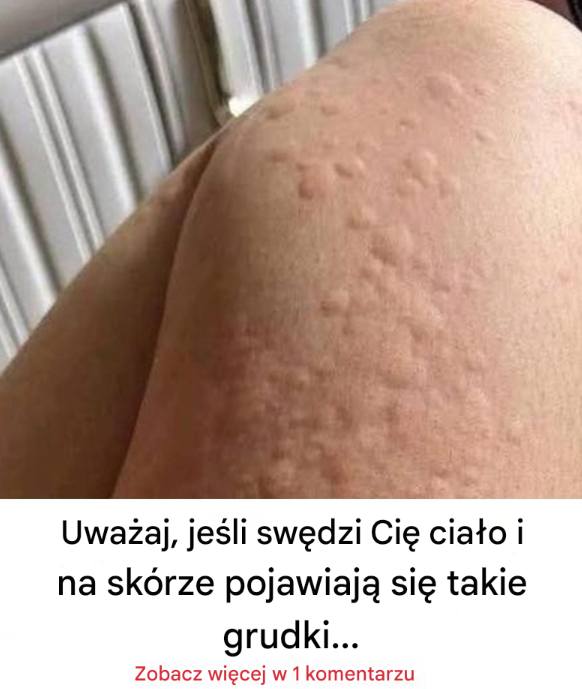

Dlaczego pokrzywka pojawia się na skórze? Oto zaskakujące czynniki, o których możesz nie wiedzieć. Pokrzywka to choroba skóry charakteryzująca się pojawieniem wypukłych, czerwonych…